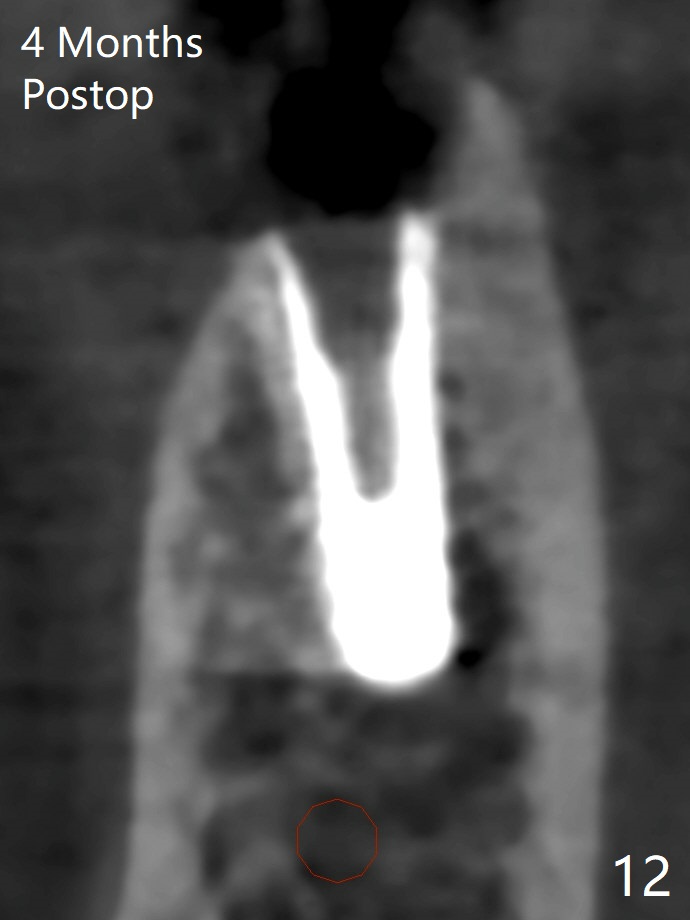

The extraction socket of #31 has a thin septum (Fig.2), which is removed partially with 12 mm bone trimmer (Fig.3). After placement of a 5x9 mm FC implant (~40 Ncm) and 6 mm bone profile drill, a 5.5x4(2) mm abutment is incompletely seated (Fig.5 <) and later is changed to a 4.5x1 mm temporary abutment (Fig.6, 8 T). The latter is used to fabricate a provisional, which in turn supports the distal papilla (Fig.8 *). The gingiva is slightly erythematous immediately post periodontal dressing removal (3 weeks postop, Fig.9). Take CT to confirm whether the cortical drill helps keep the #29 implant lingual. Use a profile drill at #29 if crestal bone loss is not obvious. There is bone coronal to #29 implant 4 months postop (Fig.10). Upon incision, the ridge is rounded (Fig.10'), but the implant appears to be buccally placed (Fig.10'' (post high speed handpiece and 5.5 mm profile drill)). The latter is confirmed by CT (Fig.12, as compared to design (Fig.11)). In spite of use of cortical drill coronally, the implant is still deviated buccally due to contrasting deferential bone density linguobuccally (Fig.13). By comparison, there is no such bone density differential involving an immediate implant at #31; the implant is placed in the socket without contacting the buccal or lingual cortices (Fig.14). The final implant is the same as expected (Fig.15). To avoid implant deviation in the lower premolar region, leave the root in place until osteotomy is finished. Five months postop, the temporary and healing abutments at #31 and 29 change to pair ones (Fig.16). Since there is limited clearance from the crestal bone, smaller abutments are used with the apparently same degree of seating (Fig.17). The abutments are prepared due to the mesial (#31) and buccal (29) tilt before impression.